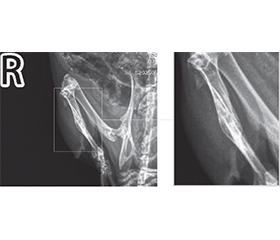

Актуальність. На сучасному етапі продовжуються експериментальні дослідження та клінічні спостереження з метою розробки нових методів лікування для покращення загоєння переломів кісток. В епоху зростання захворюваності на первинні злоякісні й метастатичні пухлини кісток, а також у часи травматичної епідемії під час війни вивчення можливостей впливу на перебіг кісткової репарації з метою її прискорення або покращення є обґрунтованим напрямом експериментальних досліджень. Мета: вивчити вплив модулюючих факторів — інфрачервоного лазерного випромінювання, кальцитоніну та пробіотика на основі Bifidobacterium animalis — на загоєння кісткового дефекту в експерименті in vivo. Матеріали та методи. В експерименті in vivo вивчено репаративний остеогенез у 32 тварин (щури Wistar), великогомілкову кістку яких травмували стоматологічним буром, використовуючи кетаміновий наркоз. Вплив модулюючих факторів на формування кісткової мозолі оцінювали за допомогою дослідження ушкоджених кінцівок тварин з використанням рентген-діагностичної системи Toshiba Radrex потужністю 80 кВт із дозою випромінювання при цифровій рентгенографії 0,03 мЗв; укладка вентродорсальна (на животі, спиною наверх), а також права латеральна (бокові зйомки). Результати. Дослідження показало, що формування кісткової мозолі під впливом лазера йде активно, але нелінійно і не завжди симетрично, що перекликається з результатами, отриманими в інших дослідженнях. У цій роботі вперше приділено увагу вивченню поєднаного впливу одразу декількох модулюючих факторів на репаративний остеогенез, а саме лазерного випромінювання, гормону кальцитоніну й пробіотика. Слід зазначити, що максимальний стимулюючий вплив на формування кісткової мозолі в експериментальних тварин спостерігався в групі «лазер + кальцитонін», що можна охарактеризувати навіть як надмірну репаративну активність кісткової тканини. Натомість у групах, де був присутній пробіотик, репаративний остеогенез у щурів проходив більш гармонійно, демонструючі кращі рентгенологічні результати, як, наприклад, у групі «кальцитонін + пробіотик» і особливо в групі, де препарат B.animalis був поєднаний із лазером та введенням кальцитоніну. Можна обґрунтовано припустити, що здатність B.animalis нормалізувати кальцієвий метаболізм створює умови для репаративного остеогенезу, максимально наближеного до фізіологічного сценарію. Висновки. Поєднання кальцитоніну з пробіотиком, а також лазерного випромінювання з кальцитоніном і пробіотиком сприяло гармонійному репаративному остеогенезу, що підтверджується відповідною рентгенологічною картиною. Здатність B.animalis зменшувати інтенсивність системного запалення, а також модулювати всмоктування кальцію з кишечника і впливати на його метаболічні шляхи може бути передумовою досягнення повноцінної кісткової репарації.

Background. At the present stage, experimental studies and clinical observations are continuing to develop new treatment methods for improvement of bone fracture healing. In the era of increasing incidence of primary malignant and metastatic bone tumors, as well as in times of traumatic epidemics during the war, studying the possibilities of influencing the course of bone repair in order to accelerate or improve it is a justified direction of experimental research. Objective: to study the influence of modulating factors — infrared laser radiation, calcitonin and probiotic based on Bifidobacterium animalis — on the healing of a bone defect in an in vivo experiment. ­Materials and methods. Reparative osteogenesis was studied in 32 animals (Wistar rats) whose tibia were injured with a dental drill using ketamine anesthesia. The influence of modulating factors on the formation of bone callus was assessed by studying the injured limbs of animals using the Toshiba Radrex X-ray diagnostic system, with a power of 80 kW, a radiation dose during digital radiography of 0.03 mSv, ventrodorsal positioning (on the stomach, back up), as well as right lateral (side views). Results. The study showed that the formation of bone callus under the influence of the laser is active, but nonlinear and not always symmetrical, which is in line with the results obtained in other studies. Instead, this work for the first time paid attention to the study of the combined effect of several modulating factors on reparative osteogenesis, namely laser irradiation, calcitonin and probiotic. It should be noted that we observed the maximum stimulating effect on the formation of bone callus in experimental animals in the laser + calcitonin group, which can even be characterized as excessive reparative activity of bone tissue. On the other hand, in the groups where a probiotic was present, reparative osteogenesis in rats proceeded more harmoniously, demonstrating better radiological results, such as in the calcitonin + probiotic group and especially in the group where the B.animalis preparation was combined with laser and calcitonin administration. It can be reasonably assumed that the inhe­rent ability of B.animalis to normalize calcium metabolism creates conditions for reparative osteogenesis, as close as possible to the physiological scenario. Conclusions. The combination of calcitonin with a probiotic, as well as laser irradiation with calcitonin and a probiotic promoted harmonious reparative osteogenesis, which is confirmed by the corresponding radiological picture. The ability of B.animalis to reduce the intensity of systemic inflammation, to modulate calcium absorption from the intestine and influence its metabolic pathways may be a prerequisite for achieving complete bone repair.